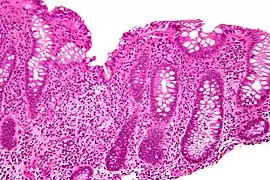

Micrograph showing cryptitis in a case of Crohn's disease. H&E stain.

In histology, cryptitis refers to inflammation of an intestinal crypt.

Cryptitis is a non-specific histopathologic finding that is seen in several conditions, e.g. inflammatory bowel disease,[1] diverticular disease,[2] radiation colitis,[3] infectious colitis.